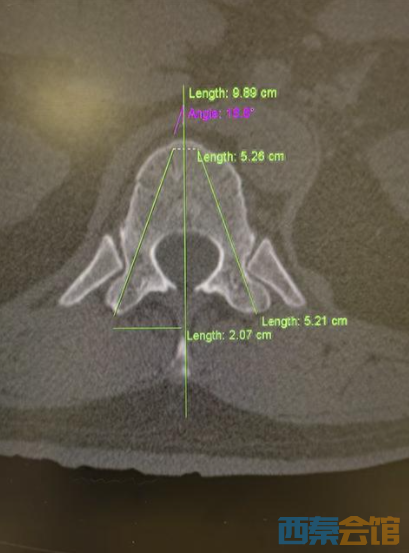

湖北日报讯(记者汪菁华、通讯员林国山)近日,45岁的周先生(化姓)从约3米高处意外坠落,臀部首先着地,当即感到腰骶部剧烈疼痛。情况紧急,他随即被送往武汉大学泰康临床学院/泰康同济(武汉)医院创伤外科,诊断为腰1椎体压缩性骨折。

患者伤情影像

针对伤情,武汉大学泰康临床学院/泰康同济(武汉)医院创伤外科主任张俊与骨科主任姚士军迅速组建救治团队,对影像学资料进行详细研判,结合患者高血压病史,综合评估骨折稳定性及神经受压风险。经讨论,团队决定采用经皮椎弓根钉棒复位内固定术。该术式属微创范畴,可在实现骨折复位固定的同时,最大限度减少对腰背部肌肉及软组织的损伤,有利于患者术后早期功能锻炼及快速康复。